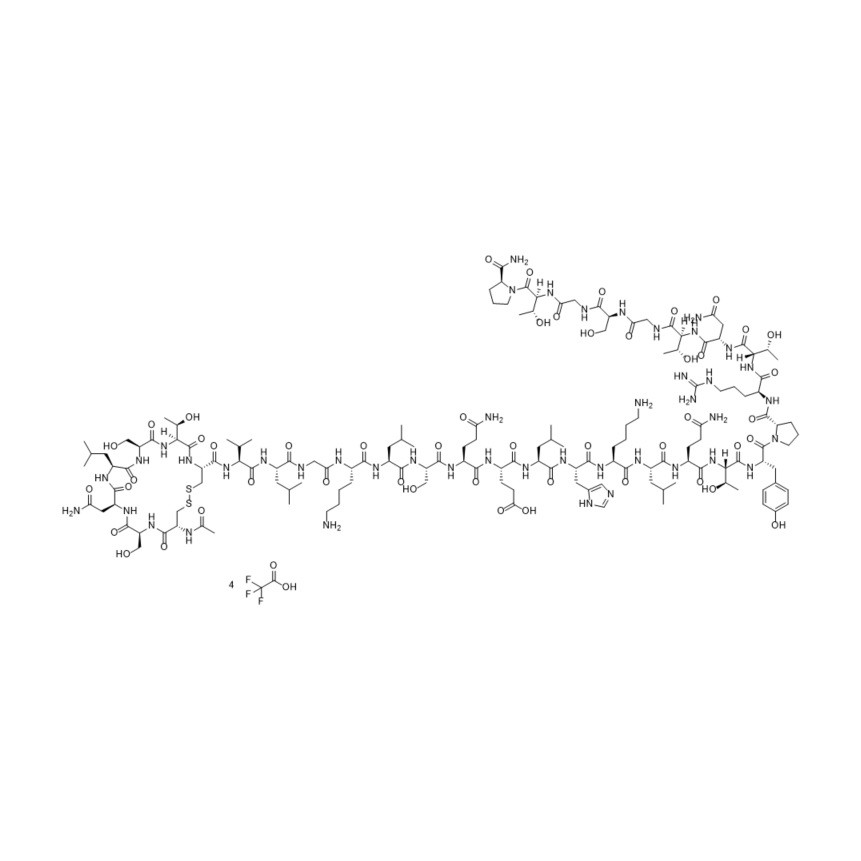

N-Acetyl-cys(1)-calcitonin Salmon Trifluoroacetic Acid

M.F.

M.W. 3474.94 ; 4(114.02)

CAT# AR-C05204

CAS# NA